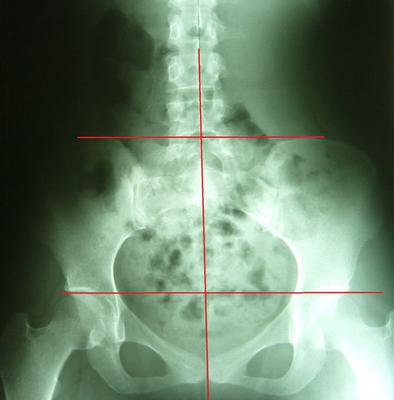

理想骨盆相对位置:两边骨盆、股骨头对称等高、中线穿过腰椎荐椎与耻骨联合、骨盆环呈现对称心形